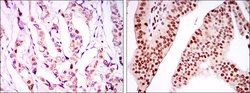

Immunohistochemistry

ABIN969370 IHC

Other validation